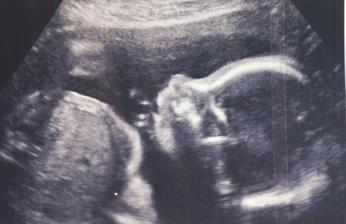

Rok 2017 v lednu mi našel car dárkyni vajíček s tím, že vše proběhne v únoru. Mezitím jsme dostali výsledky z imunologie a v krvi mám zvýšené NK buňky, což jsou buňky které vypuzují vše cizí z těla, tedy embrya. Takže mi byly předepsány nitrožilně intralipidové infuze. První týden před ET druhá týden po a posledni týden po pozitivním tt. No a teď k únoru, první infuze byla za mnou vse jsme zaplatili, dárkyni odebrali vajíčka a druhý den na Valentýna mi volala dr, ze má špatnou zprávu. Z 28 odebraných folikulů nebylo ani jedno vajíčko. Takže mi najdou novou dárkyni, a taky že našli, asi za hodinu mi volali, že už jí maji a odsouvá se to celé na březen 2017. ET je naplánovaný na 11.3.2017. Transfer probehl v poradku a ja doufsla, ze ted uz to konecne vyjde. Cekani do testu bylo umorne, po 11.dnech jsem to uz nevydrzela a udelala jsem ho. Nechala ho lezet v kuchyni na stole a bala jsem se na nej jit podivat, kdyz jsem se odhodlala nemohla jsem uverit!! Takovy dalnice!!! Hned jsem zacala bulit 😀 byl to krasny pocit po tom vsem a stale jeste je👶🏻 Byla to dlouha cesta a vime, ze jeste zdaleka nekonci.....

@verryk dekuji moc. Dnes byla kontrola a vse v poradku. Mi i je o 3 dny napred tedy 11+0 a mela sem byt 11+4